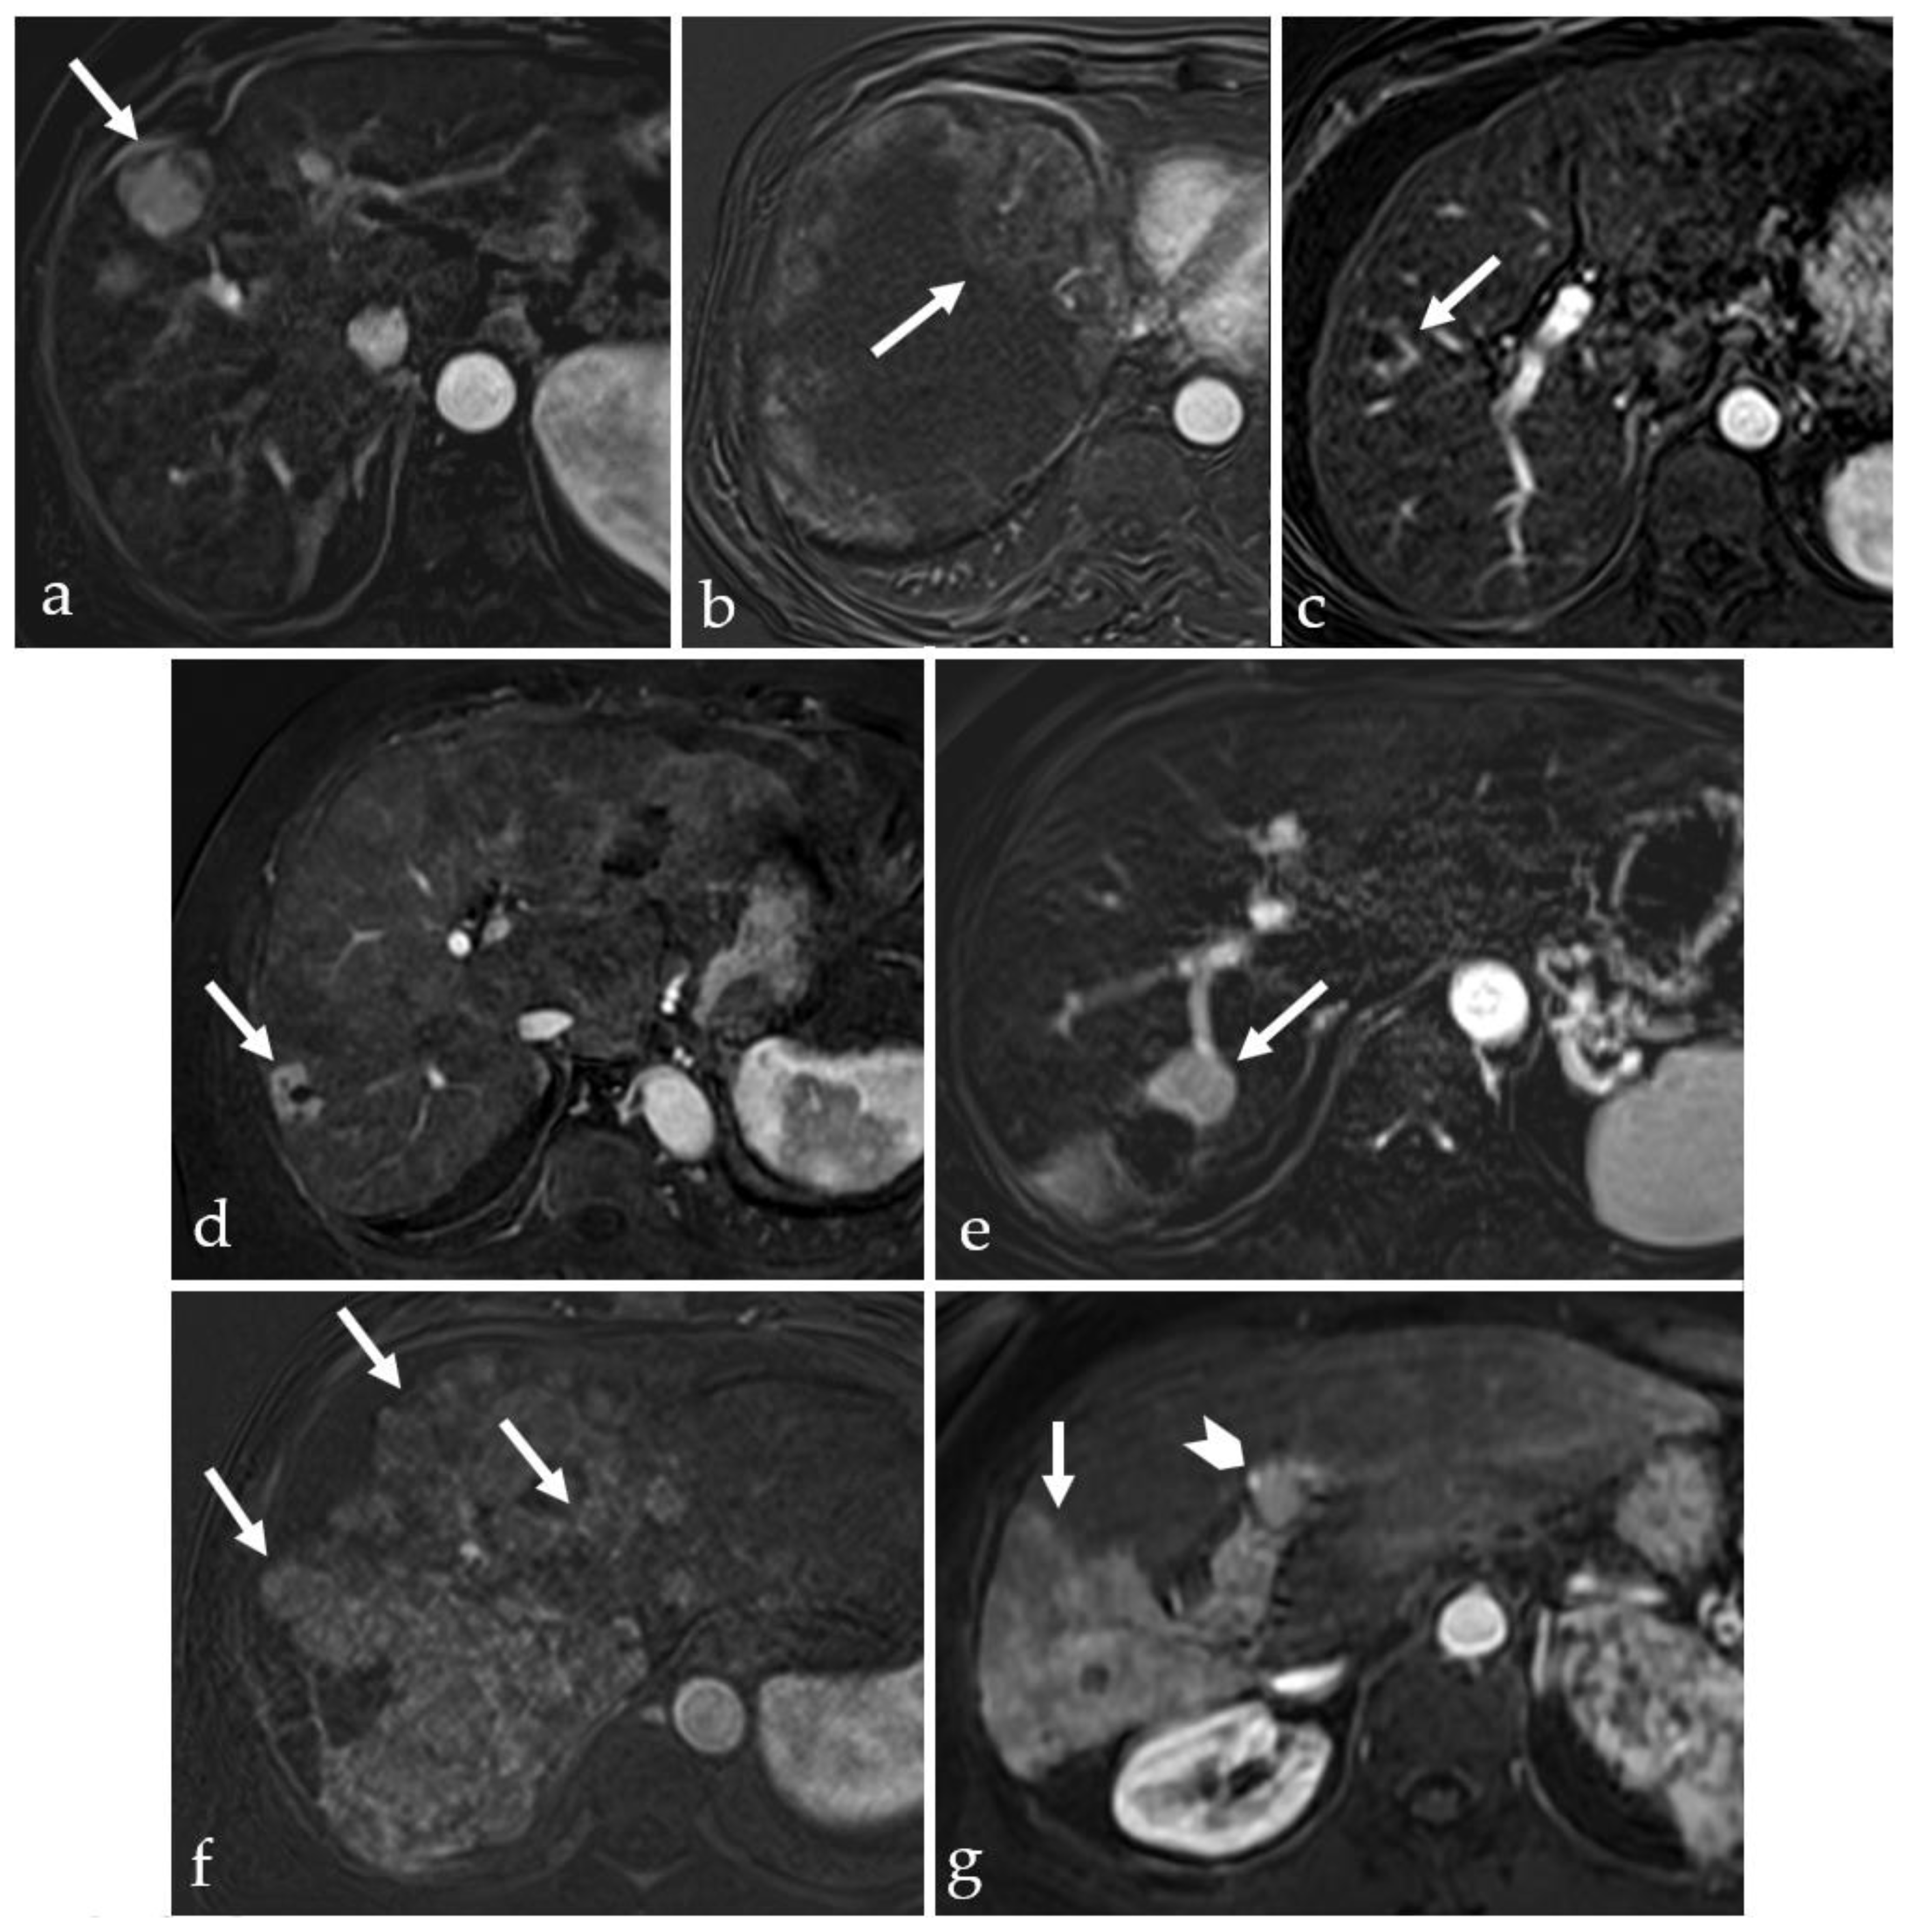

3.2. Expected Post-Treatment Imaging Features in the Absence of Viable Tumor Tissue

3.5. Post-Treatment Imaging Features of Tumor Viability